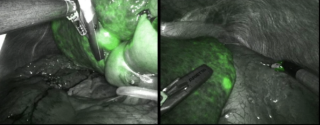

An 82-year-old otherwise healthy man was referred for evaluation of an incidentally detected left adrenal mass. The patient was asymptomatic with no clinical signs of catecholamine excess, hypercortisolism, hyperaldosteronism or B-symptoms. Initial CT scan revealed a 44 × 42 mm lesion, which increased to 50 × 46 mm within three months and suspicious washout characteristics (Figure 1). Endocrinological work-up showed a pathological dexamethasone inhibition test, while metanephrines and aldosterone testing was normal. Tumor markers (AFP, β-HCG) were unremarkable. A hormonally active adrenal adenoma with autonomous cortisol production was suspected.

After discussion at the interdisciplinary tumor board, robotic-assisted adrenalectomy was performed (Figure 2). Complete resection was achieved without complications, the patient was discharged on the third postoperative day.

Histopathological examination showed a Sertoli cell tumor with complete excision and no evidence of local infiltration or malignancy (Figure 3).